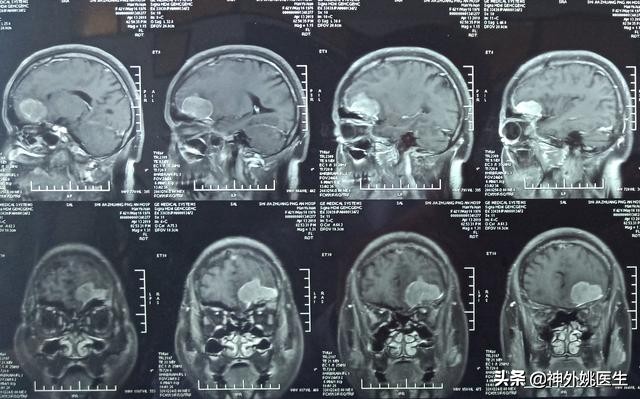

头MRI检查:1、左额部脑膜瘤。2、左侧放射冠区腔隙性脑梗死。(图3-7)

图6 增强扫描可见病变呈不均匀强化。

图7 病变基底位于颅底硬膜,可见脑膜尾征,病变大小约3.8cm x 4.1cm x 2.9cm。